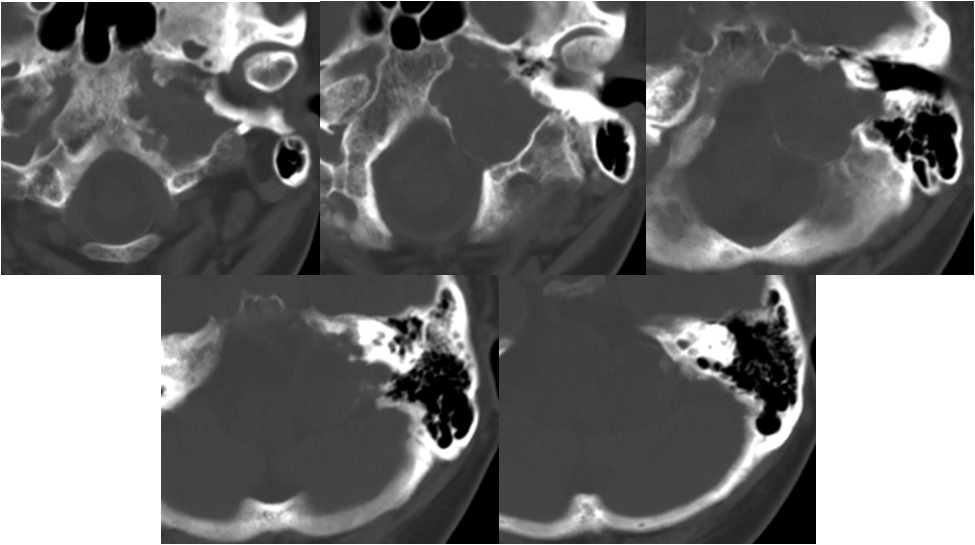

术中过程

![]()

切口体位